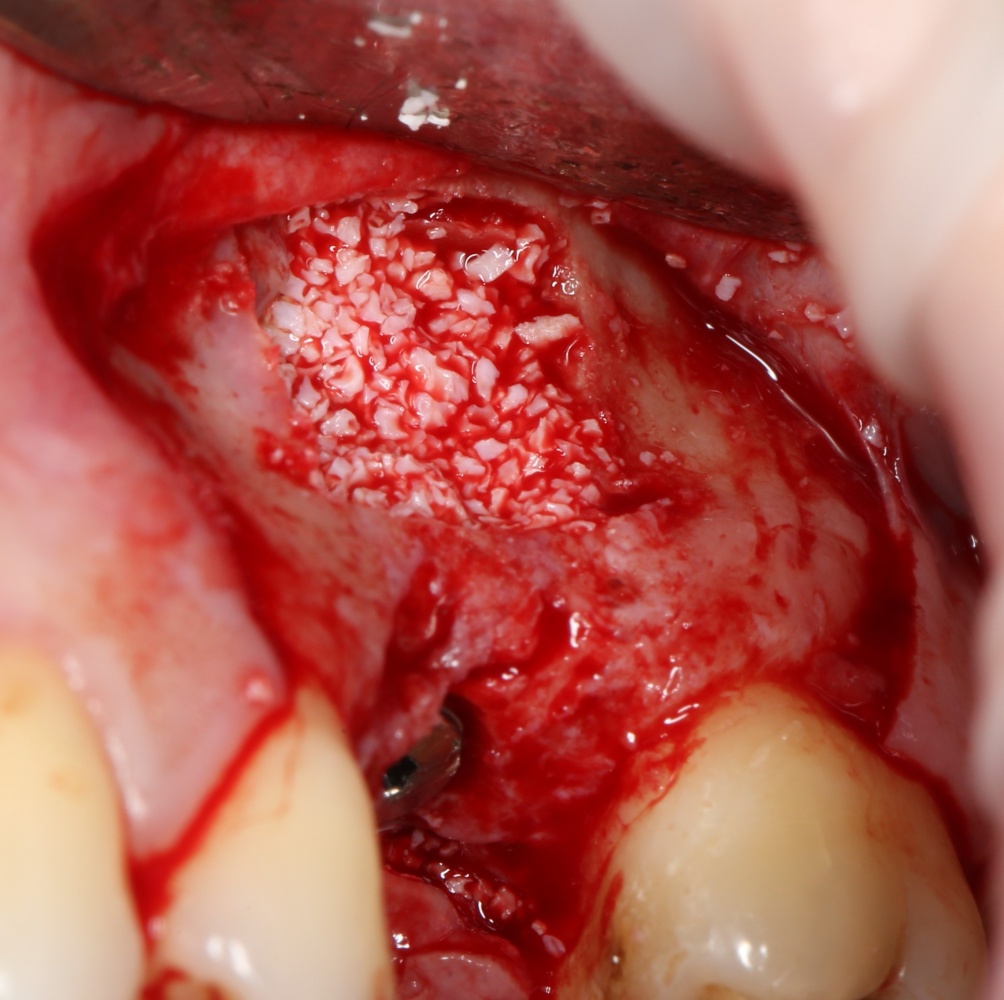

Подготовка костного ложа и фиксация аутотрансплантата

Возвращаемся к основной операционной области. Еще раз посмотрим на альвеолярный гребень, поофигеваем от его ширины и моих грандиозных планов:

На этом месте мне следует дать некоторые пояснения.

Если ты читал мои предыдущие публикации, посвященные остеопластике, то наверняка знаешь, что костное ложе перед фиксацией графта (любого графта) требует некоторой подготовки. В основном она заключается в полном или частичном удалении кортикального слоя и, применительно к АТККФ — адаптации не только блока под ложе, но и ложа под пересаживаемый костный блок. Подробности здесь>>

Ежу понятно, что к необходимости этих манипуляций мы пришли не сразу. А тогда был 2013 год… и у меня были мысли, что подготовка костного ложа нужна не всегда и не всем. Здесь я понадеялся на размер костного дефекта и большую площадь контакта между костным аутотрансплантатом и принимающим ложем. Конечно, сейчас я сделал бы немного по-другому.

Я зафиксировал костный блок практически без адаптации на несколько винтов. Обрати внимание, что винты находятся в зоне, где не планируется установка имплантатов. Фиксация должна быть надежной, поскольку мне еще предстояла подготовка лунок для имплантатов. Трех винтов для этого вполне достаточно.

Дальнейшая адаптация костного блока свелась к сглаживанию острых краев. После чего я приступил к подготовке лунок и установке имплантатов.

Изоляция области аутографта и имплантатов барьерной мембраной.

Перекрывать костный блок барьерной мембраной или оставить так? По этому вопросу есть много мнений. Между тем, в публикации по методике есть ясное показание, когда это требуется.

Конкретно в этом клиническом случае между костным аутотрансплантатом, ложем и имплантатами есть пустое пространство. Если его не изолировать от мягких тканей, они прорастут и осложнят интеграцию аутографта. Поэтому я решил перекрыть костный блок барьерной мембраной, пусть это делает хирургическую операцию немного дороже.